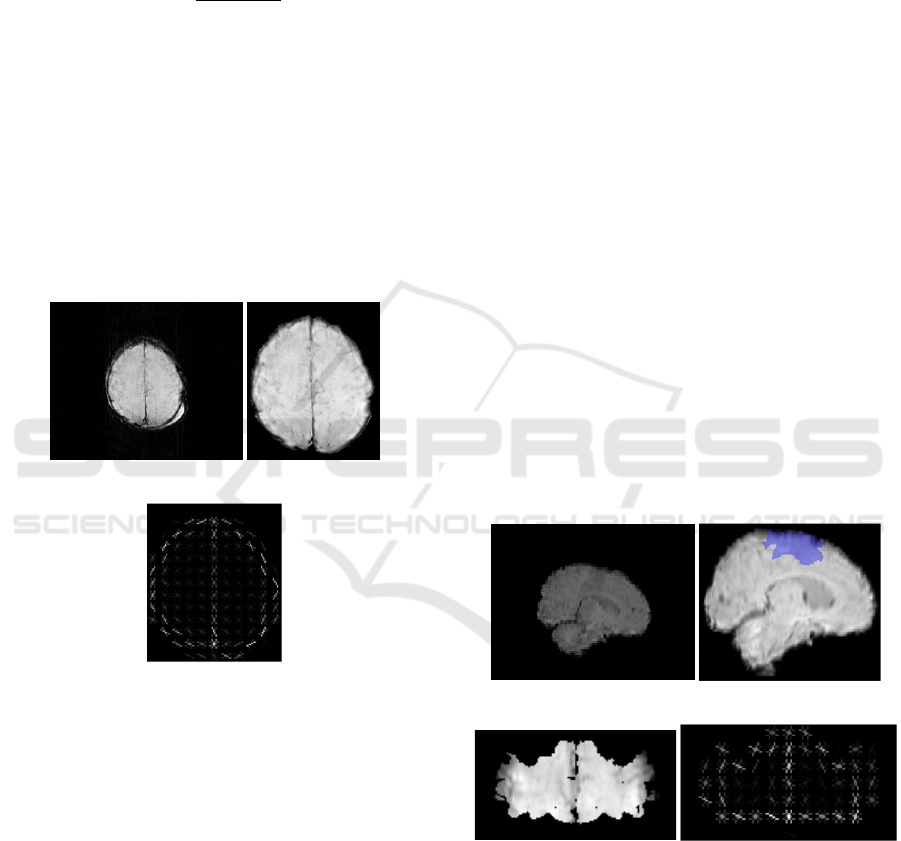

3.3 Image Registration

brain as a 3D brain were examined. As shown in

Figure 2(b), the area covered in blue represents the

motor area. The motor areas of the brain in SWI

images are therefore selected by registering SWI

images to the template brain and the motor areas are

left in the 3D image with the rest of the brain being

ignored (i.e. set to zero).

(a) (b)

(c) (d)

Figure 2: (a) Original brain image. (b) Brain image after

registration and motor area covered by blue (c) 2D image

of motor area (d) HOG of motor area.

Finally we consider the 3D motor region images

as slices and compute HOG feature vector 𝑉



associated with the motor region. In a similar fashion,

we select frontal, parietal and temporal lobes for

Hypoxic-Ischaemic Encephalopathy Prognosis using Susceptibility Weighted Image Analysis based on Histogram Orientation Gradient

59

cognitive regions of the brain by using the

aforementioned registration method. Then by only

considering these three lobes on the 3D SWIs and

ignoring the rest of the brain, we measure the HOG

feature vectors 𝑉



associated with these three

lobes.